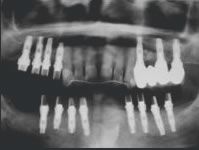

Nous maîtrisons tous les types d’implants :

Biomet 3i Encode, Biomet 3i Cam StructSURE, Simeda, Atlantis / Astra Tech, Anthogyr, Keystone, Ankylos, Nobel, Straumann, etc.

Les systèmes Biomet 3i Encode et Cam StructSURE ainsi que Simeda permettent un ajustement et une réalisation sur mesure de votre pillier implantaire.